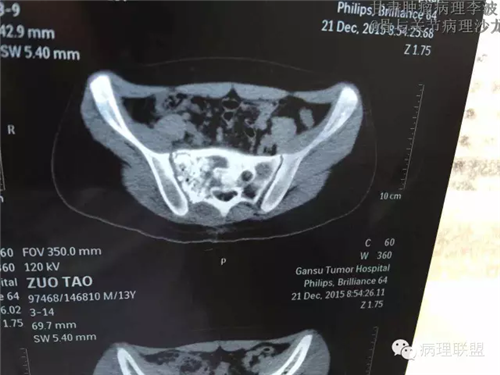

M/14 骶骨骨肉瘤-张惠箴讲解

病例由甘肃肿瘤病理 李波 提供,致谢。